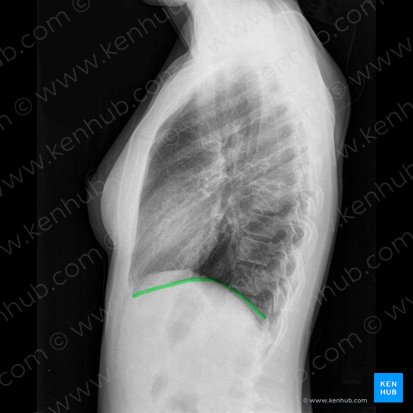

Inspiration

Idealerweise sollte die Röntgenaufnahme bei maximaler Inspirationstiefe der Patient:innen durchgeführt werden (die Lungen sollten also maximal mit Luft gefüllt und voll entfaltet sein). Ob dies der Fall ist, kann durch das Zählen der in den Lungenfeldern zu sehenden posterioren Rippen in Erfahrung gebracht werden. Wenn Patient:innen sich beim Einatmen Mühe geben, sie also einen tiefen Atemzug nehmen und für die Dauer der Aufnahme angehalten haben, sollten im Röntgenbild ungefähr 10 Rippen über dem Zwerchfell zu sehen sein.

Zwerchfell

Auch das Zwerchfell kann dir wichtige Informationen über den Gesundheitszustand von Patient:innen liefern. Normalerweise sind die beiden Zwerchfellkuppeln gewölbt. Die rechte Kuppel steht aufgrund seiner Lage direkt über der Leber etwas höher. Wenn das Zwerchfell abgeflacht aussieht, könnten Patient:innen an chronischem Asthma oder an einer chronisch obstruktiven Lungenerkrankung (COPD) leiden. Halte zudem unbedingt Ausschau nach freier Luft unter dem Zwerchfell - dies ist ein Zeichen für eine Magen- oder Darmperforation und gilt als chirurgischer Notfall.

Bei der Auswertung eines Röntgen-Thorax ist es auch wichtig, die beiden Zwerchfellwinkel (Recessus costodiaphragmatici) zu beurteilen. Bei abgeflachten Zwerchfellwinkeln erscheinen diese nicht mehr scharf begrenzt. Die Ränder sind nicht mehr deutlich zu erkennen, sondern erscheinen vielmehr gräulich-verschwommen. Dies kann auf eine Flüssigkeitsansammlung zwischen Pleura und Lungengewebe (Pleuraerguss) hinweisen. Pleuraergüsse sind manchmal nicht auf den ersten Blick zu erkennen, daher ist es wichtig, immer genau hinzuschauen. Gerade kleinere, posterior gelegene Ergüsse können auf einer lateralen Röntgenaufnahme oft leichter entdeckt werden als auf einer p.a.-Aufnahme.